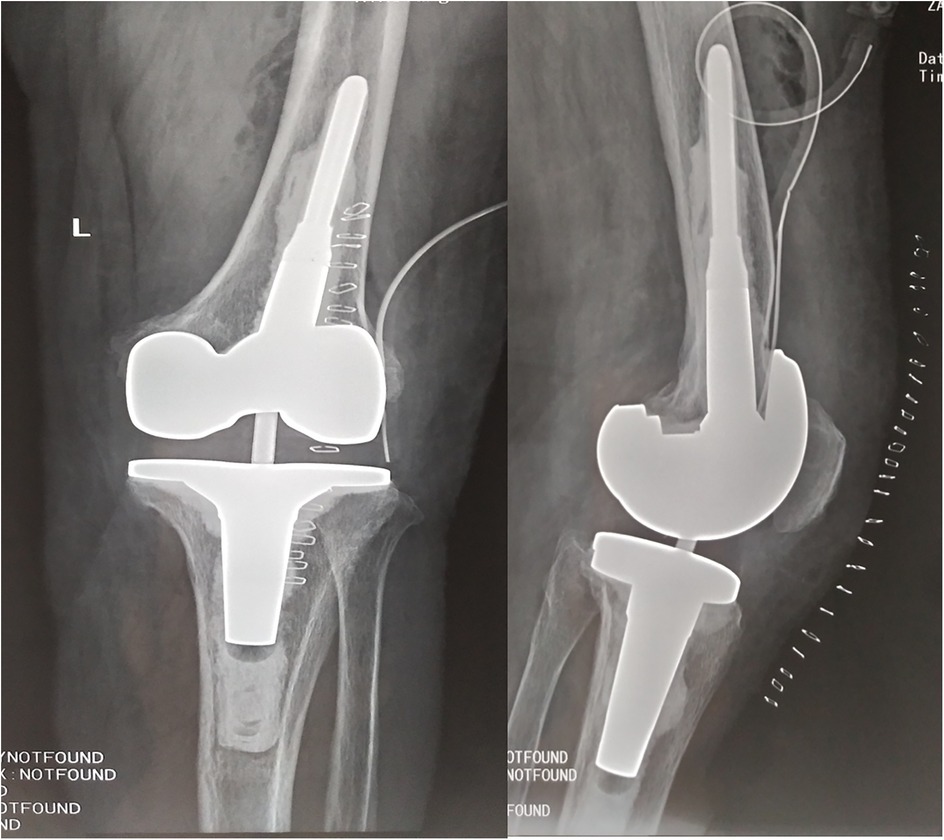

Surgical procedures were performed under general anesthesia. For knee revisions, a standard medial parapatellar arthrotomy was used with a tourniquet. For hip revisions, a posterolateral approach was employed. During the operation, purulent or necrotic tissue around the prosthesis was observed. Purulent fluid was turbid and pale yellow, with synovial hyperplasia edema and synovial partial necrosis (Figure 3). We performed debridement first; pulse pulse lavage helped to eliminate Brucella bacillus. After this step, the gloves were changed, and a new operation instrument was used for revision. After debridement and installing the prosthesis, pulse lavage was performed after the bone cement was dry, and doxycycline powder (100 mg) was used directly around the prosthesis. No drainage tube was placed. The most conclusive means of establishing a diagnosis of brucellosis is positive cultures from normally sterile body fluids or tissues. During the operation, pus was cultured, and the tissues were removed and sent for routine pathological examination. Synovial fluid and tissue samples were collected for Brucella culture on specific media and PCR analysis using species-specific primers. Post-operation x-ray exam shows good position of prosthesis (Figure 4), and patients feel good also have good function (Figure 5).

Figure 4. Post-operation x-ray shows no prothesis loosening happened, implants placed good position.